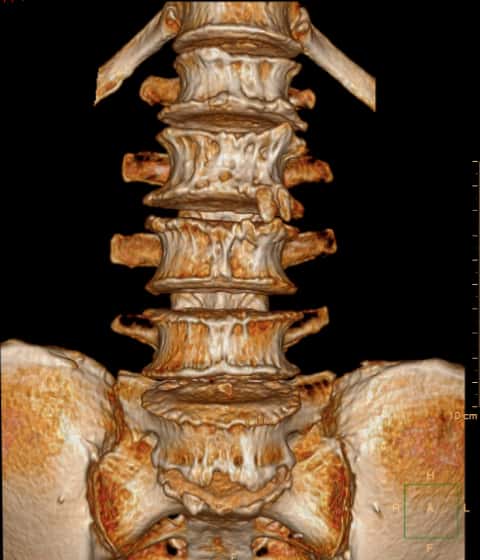

那么再看看患者的CT和MRI。问题并不简单。1997年因腰椎间盘突出,于北京XH医院行腰椎后路手术

腰椎退变增生

重建的片子上看不到太多的手术痕迹。

腰4/5水平,小关节及关节后方有大量的增生

腰4/5水平,小关节及关节后方有大量的增生。

多个腰椎小关节及关节后方有大量的增生。